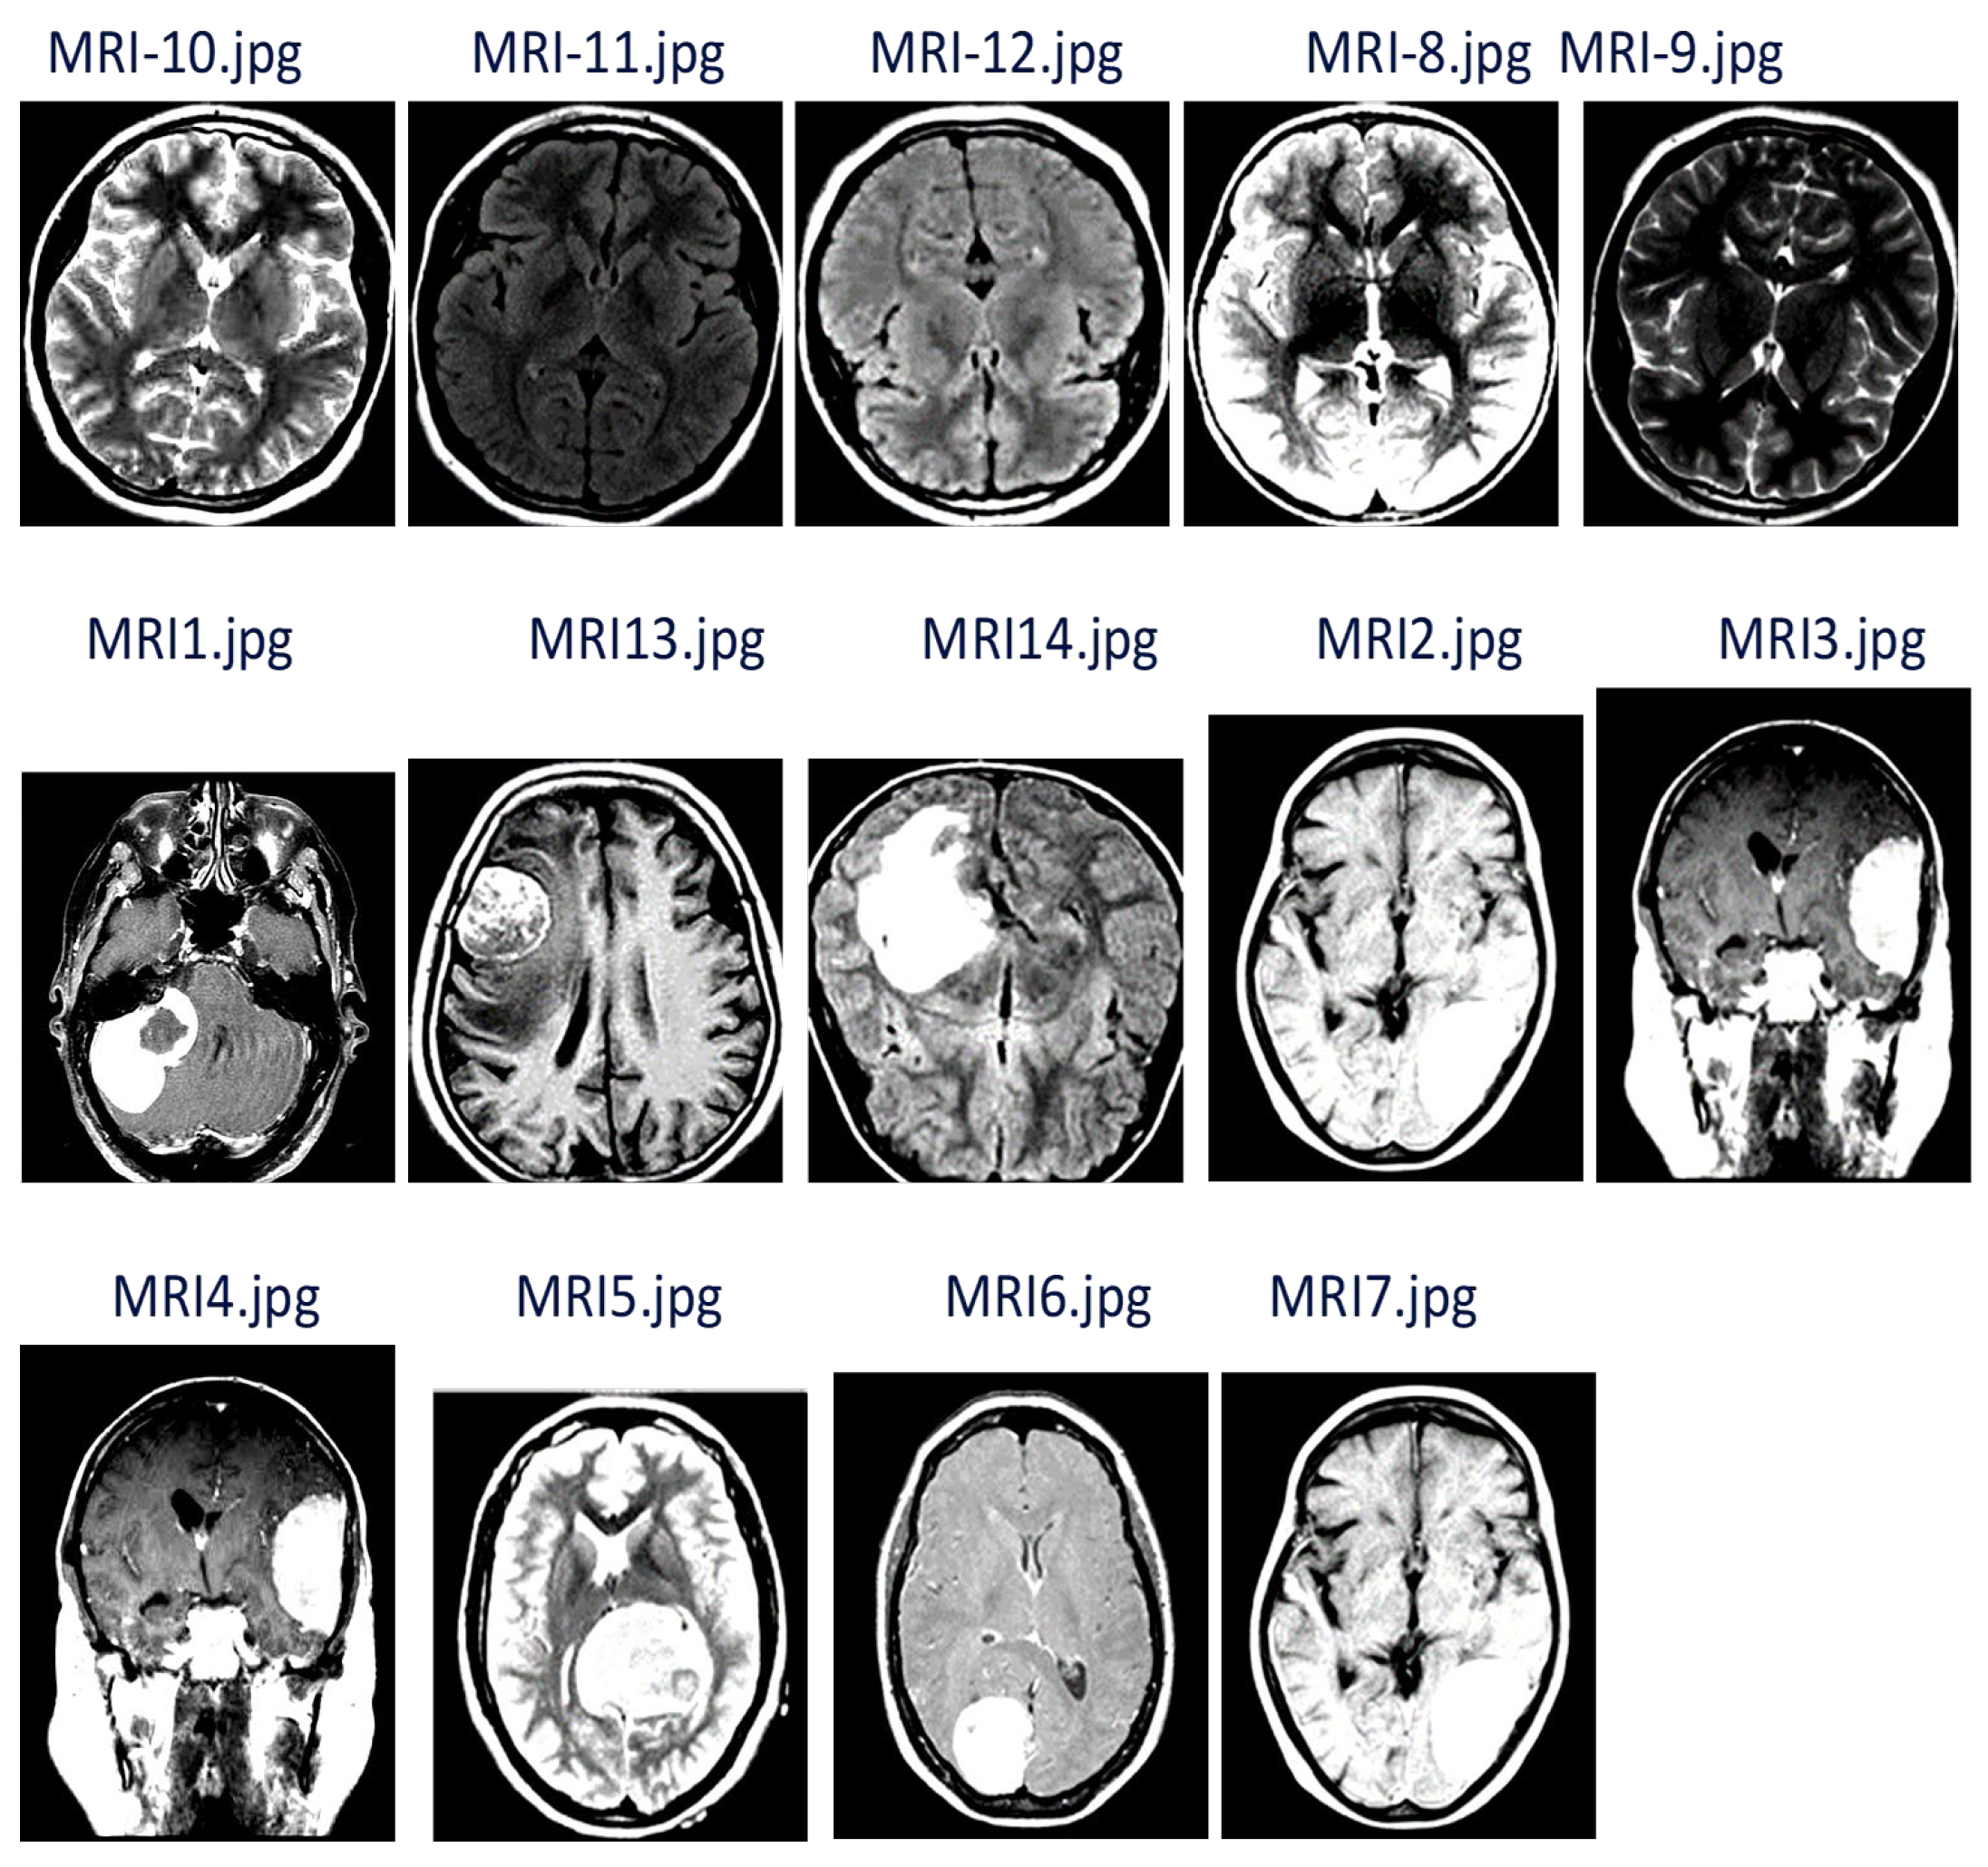

| Test MRI Image Sample | Improved MRI Samples | Feature of MRI Samples | Classification Result | |

|---|---|---|---|---|

| Cluster 1 (Normal) | Cluster 2 (Tumor) | |||

![]() | ![]() | ![]() | ![]() | |